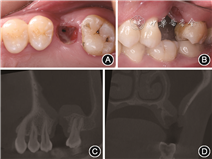

(2) 临床检查:见图1。口内检查示26牙缺失,牙槽嵴颊侧凹陷,垂直向高度缺损严重,拔牙窝未愈合,洞壁内可见炎性肉芽组织,基底可见约2 mm×3 mm大小的穿孔,与上颌窦相通。27稍向近中倾斜,36未见明显伸长。锥形束CT显示26缺牙区牙槽骨缺损严重,颊侧骨板缺如,对应上颌窦底约5.3 mm×5.5 mm大小骨缺损,上颌窦底黏膜增厚明显,约8 mm,未见囊肿或其他病理表现。

面观;B:口内颊面观; C:锥形束CT矢状面;D:锥形束CT冠状面

面观;B:口内颊面观; C:锥形束CT矢状面;D:锥形束CT冠状面(3)诊断:26口腔上颌窦瘘;上颌牙列缺损。